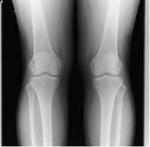

ひざの痛み/鵞足炎

【実例】鵞足炎/膝の痛み

「レントゲン、MRI検査をするも原因がわからない」

ひざの痛み【鵞足炎】は、

縫工筋と薄筋、半腱様筋、3つの筋肉が付着するひざの内側に痛みを起こします。

レントゲン、MRI検査で全ての原因を理解する事は出来ません。

なぜなら、筋肉と筋膜の事は分からないからです。